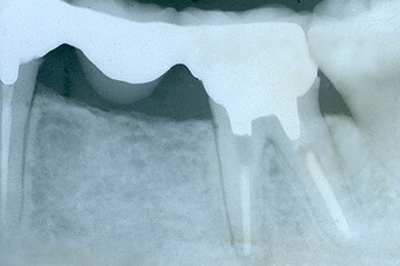

インプラント施術例

歯を削りたくない、入れ歯をどうしても入れたくないという時、インプラント治療を行っています。

レントゲン